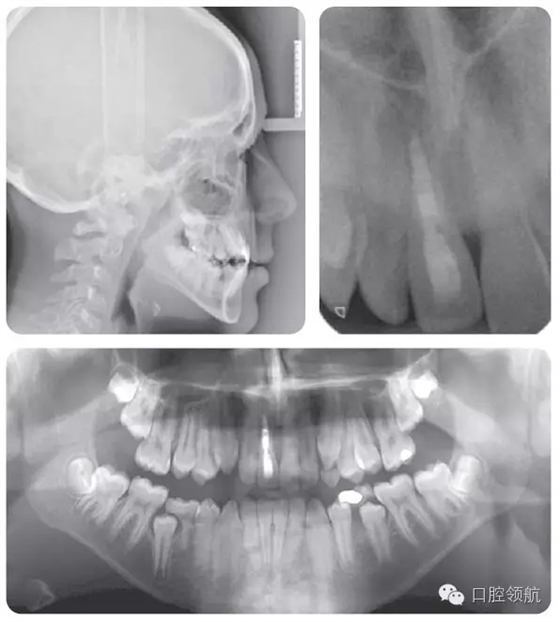

牙根外吸收可以通過(guò)牙齒的松動(dòng)度來(lái)判斷。在一些病例可能發(fā)生根骨粘連,并且牙齒位置較鄰牙常表現(xiàn)為未能萌出至平面。叩診該患牙呈高調(diào)、濁音。正畸力往往難以使該牙產(chǎn)生移動(dòng)。臨床和X線片檢查(圖2.47)顯示該患者的UR1發(fā)生了根骨粘連。

● UR1根骨粘連,牙冠變色。